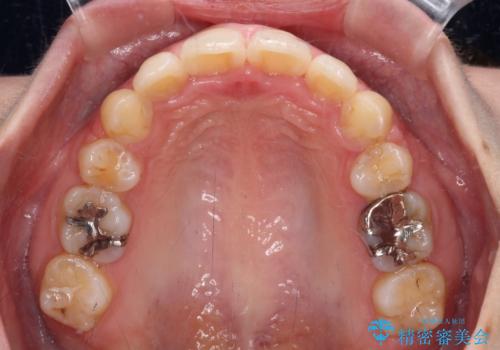

ご友人などがびっくりするほど口元の突出感を改善することができ、患者様には大変満足していただきました。